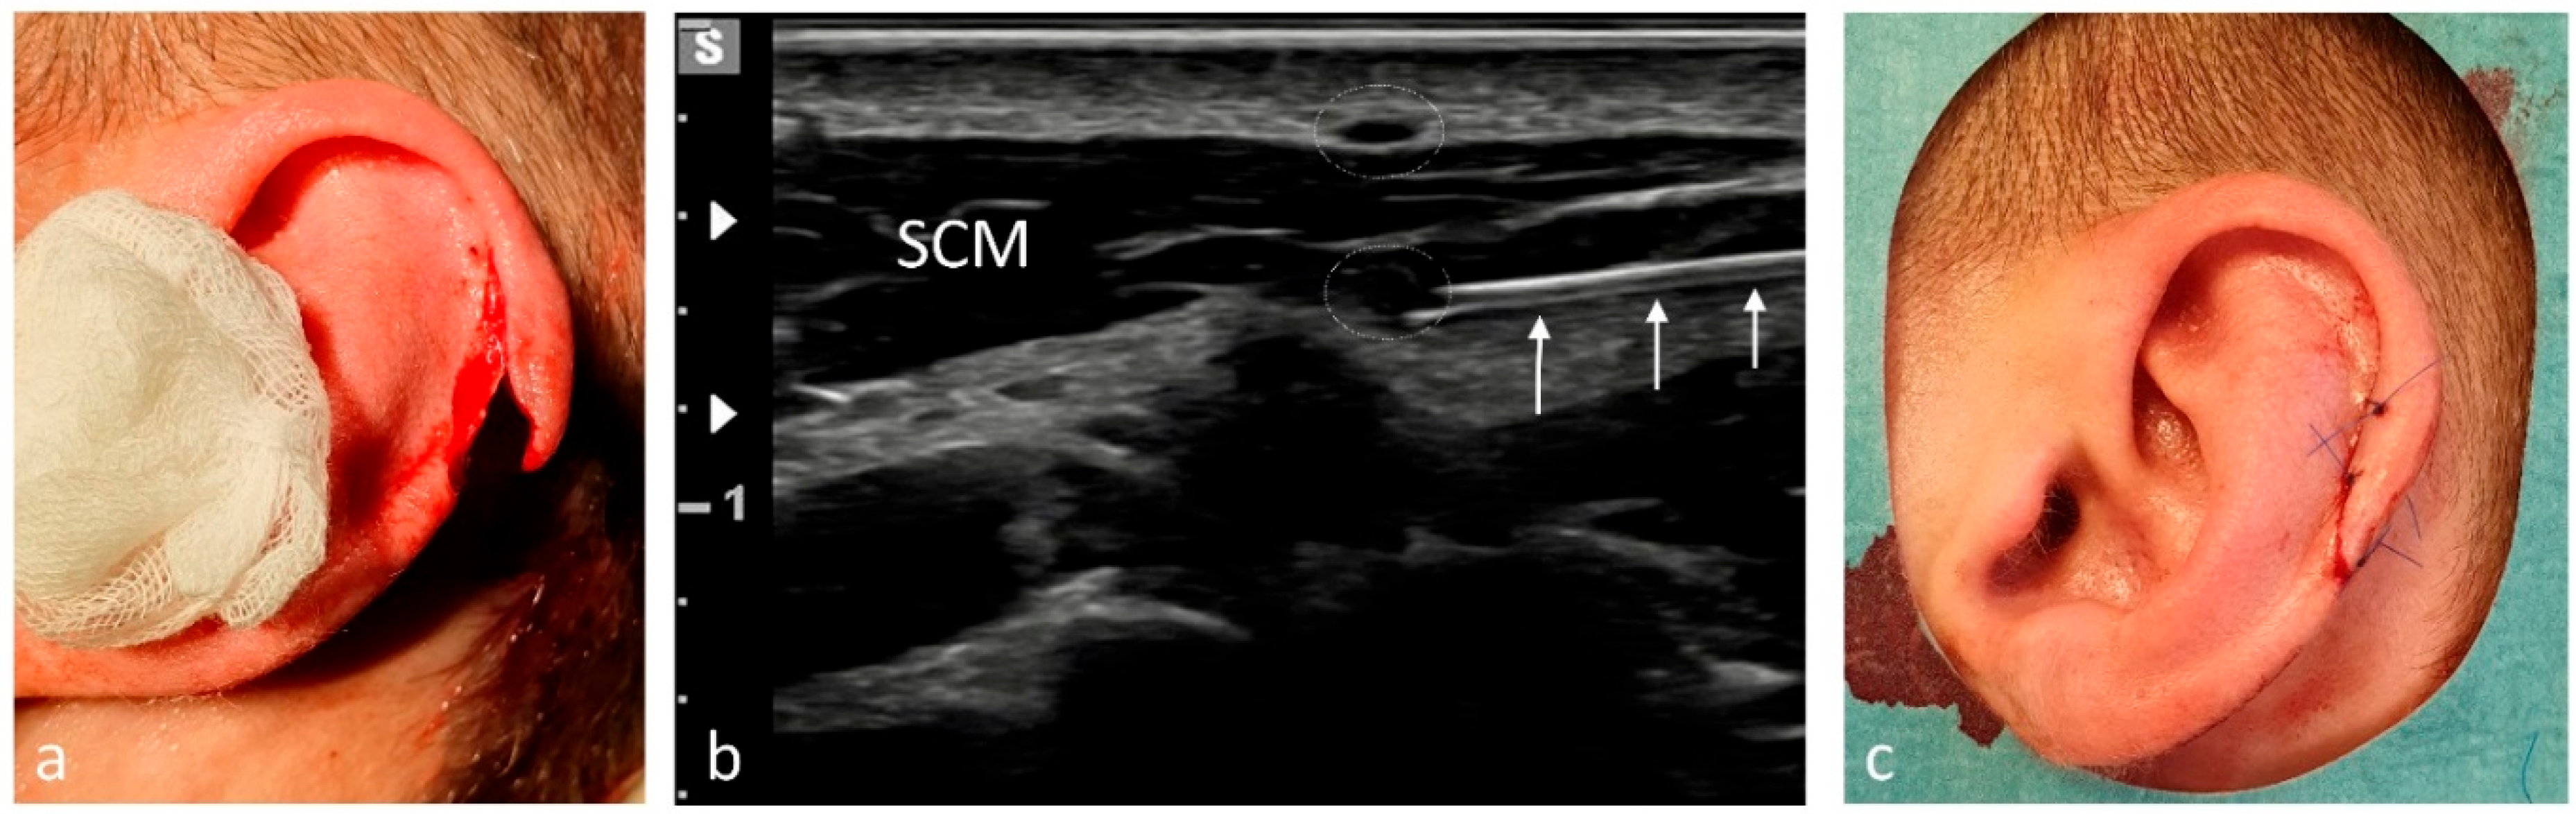

| AC joint | 11 | Supraclavicular nerves/2–3 |

| Fingers | 8 | Hand block (ulnar, median, superficial radial)/2–3 per nerve |